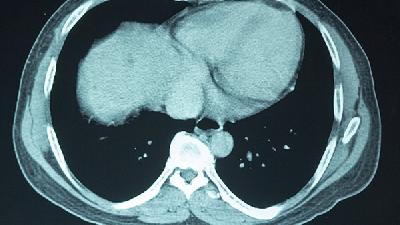

主要是由于脑肿瘤这种疾病近些年严重影响到人们的生活和身体健康,所以越来越多的人开始关注这种疾病,积极进行预防工作,那么下面为了大家能够尽早发现自己患病,那么脑癌的检测指标都有什么?1.影像学检查包括头颅X线摄片、放射性核素脑造影、脑室和脑池造影、脑血管造影等。这些检查过去曾是神经系统疾病的重要诊断方法,不仅具有病变定位的意义,还有一定的定性诊断价值。但是这些...

脑癌的检查有哪些具体项目?临床上对于恶性脑瘤的诊断,不仅仅是确认肿瘤的性状,检查目的还包括,观察肿瘤的生长部位、转移程度、以及对患者身体的伤害程度等等。所以,脑癌患者一定要做好各方面详细的检查。下面就是临床上一些常见的检查方法。确诊脑癌必要的检查项目虽然没有特定的临床症状可以直接判定恶性脑肿瘤的发生,但局部神经症状例如颅内压的产生和加重时则须相当注意,或是没...